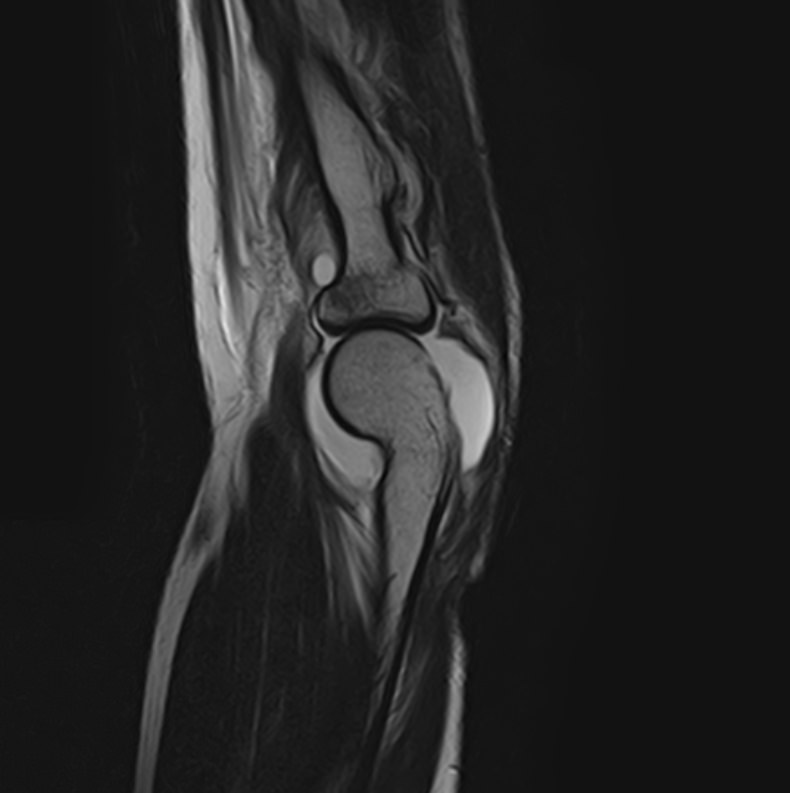

Локтевой сустав представляет собой подвижное сочленение плечевой кости с лучевой и локтевой костями предплечья. Сочленение имеет сложное строение и состоит из трех суставов, заключенных в одной составной капсуле. Сустав выполняет несколько видов движений и испытывает интенсивные нагрузки, поэтому часто подвергается травматизации и развитию различных заболеваний, в том числе, воспалительных и дегенеративно-дистрофических. Болевой синдром в локтевом суставе, который возникает при многих патологиях, требует проведения дифференциальной диагностики с помощью высокоточных методов обследования.

Магнитно-резонансная томография является наиболее информативным методом диагностической визуализации всех структур локтевого сустава, включая костные структуры, связки, сухожилия, прилегающие мягкие ткани. По сравнению с другими методами обследования, такими как УЗИ, рентгенография и компьютерная томография, МРТ позволяет получить наибольшую информацию о патологических процессах в суставе и окружающих тканях, поставить точный диагноз и определить тактику лечения. При этом МР томография не оказывает вредного воздействия на организм, так как технология процесса не предусматривает использование рентгеновского излучения.

В клинике «Доступная медицина» проводится МРТ локтевого сустава на современном томографе закрытого типа TOSHIBA VANTAGE TITAN 1,5 Тесла. Благодаря высокой мощности магнитного поля устройство при сканировании выявляет даже минимальные очаги поражения сустава и на основе полученных данных проводит построение 3D-модели. Кроме того, для увеличения информативности МРТ в некоторых случаях применяется введение контрастного вещества, содержащего в своем составе металл гадолиний.

Что показывает МРТ локтевого сустава

При глубинном и тщательном исследовании, МРТ обеспечивает легкое обнаружение ряда проблем, которые достаточно сложно диагностировать визуально, посредством анализов или других методик диагностики. Иногда это сделать вовсе невозможно. Без оперативного вмешательства, с помощью МРТ локтевого сустава можно определить: